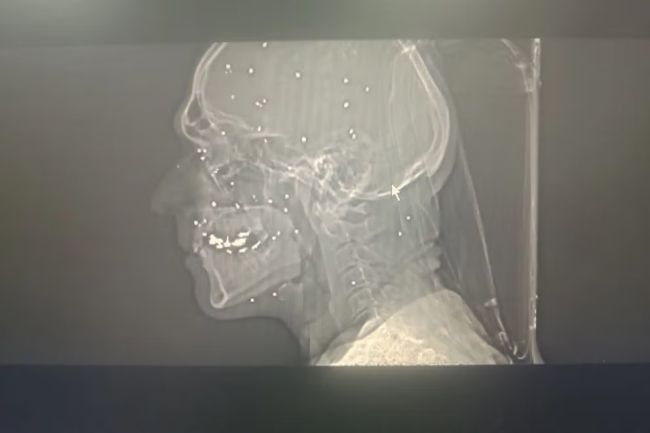

روی صورت «آناهیتا»، نقطه‌های سفید مانند یک صورت فلکی دیده می‌شود. نقاطی که در حفره‌های چشم، روی گونه و پیشانی و حتی در بخش‌هایی از مغز پراکنده‌اند. هر نقطه، یک ساچمه فلزی است که در تصاویر سی‌تی‌اسکن ثبت شده است. این ساچمه‌ها که از شاتگان شلیک می‌شوند، در فاصله نزدیک می‌توانند استخوان را خرد کرده و به‌راحتی به کره چشم نفوذ کنند.

آناهیتا که در اوایل دهه سوم زندگی خود است، دست‌کم یک چشم و احتمالا هر دو چشمش را از دست داده است.

تصویر او یکی از بیش از ۷۵ مجموعه تصویر پزشکی شامل رادیولوژی و سی‌تی‌اسکن است که از یک بیمارستان در یکی از شهرهای بزرگ ایران به دست آمده و در اختیار گاردین قرار گرفته است. تصاویری که در طول یک شب و هم‌زمان با سرکوب اعتراضات دی‌ماه ثبت شده‌اند.

تصاویر، روایتی از شدت خشونت علیه معترضان و رهگذران ارائه می‌دهند.